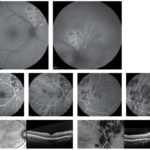

Presentazione e gestione di un caso di coroidite serpiginosa TB correlata